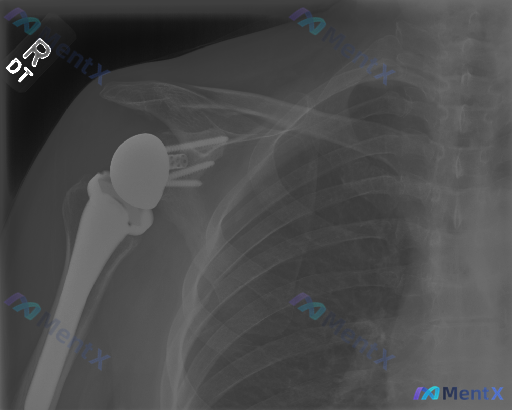

这张右肩关节置换术后X光片,能看到明确的病理性异常吗?

整理了一份右肩关节置换术后的影像学分析资料,先把核心影像表现放出来,看看大家第一眼的读片思路会怎么走。 影像核心所见(仅基于这份单时点X光): - 可见右肩关节假体(肱骨侧柄+球头、关节盂侧底座+螺钉),位置在位 - 假体-骨界面贴合紧密,未见明显透亮线(松动征象) - 关节对位正常,无半脱位/移位...